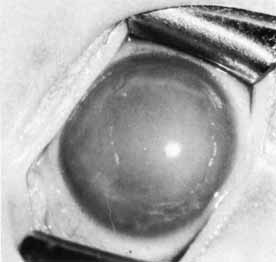

Primary congenital glaucoma presents clinically with epiphora, photophobia, and blepharospasm. Examination often reveals increased corneal diameter, corneal cloudiness (Fig. 12), and breaks in Descemet's membrane. Other findings include an intraocular pressure greater than 21 mm Hg, isolated trabeculodysgenesis on gonioscopy, and increased optic nerve cupping.

Fig. 12 Primary congenital glaucoma. Buphthalmos and corneal clouding.